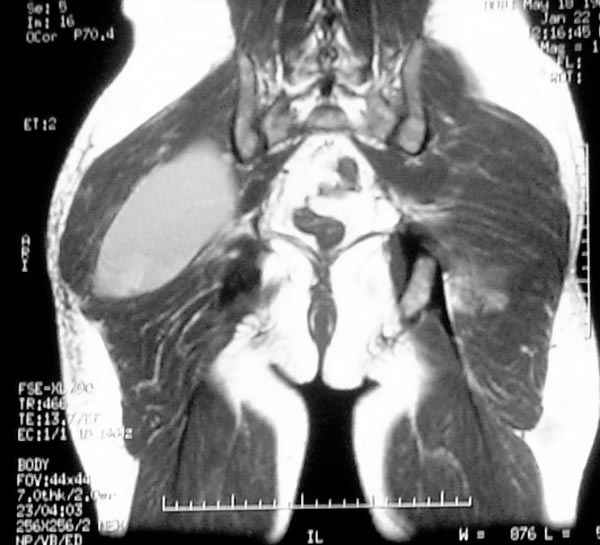

Уважаемые коллеги,Неоднократные пункционные эвакуация (3 раза) крови изягодичной области, после полученной пройзводственнойтравмы (более 1.5 мес) ударом в ягодицу тяжелым, около полутонны предметом.

Рентгенограмма без особенностей, несмещенные переломы лонной и седалищных костей таза.Последная пункция 10 дней назад 180 мл темной крови, после пункции сделано магнито-резонансные исследование (на снимках), какой диагноз и тактика дальнейшего лечения, какие рекомендации?Джолдас Кульджанов

Djoldas Kuldjanov, M.D. 06 Март 2005, 00:25

Разбираемый случай немного отличался от классического Degloving Injury

или Morel-Lavalle Lesion, которые часты при переломах ацетабулума и

костей таза. Состояние, наблюдаемое после удара, в результате чего

образуются обширные полости в тазобедренной области: ягодицы или

большого вертела. Как описал Анатолий, обширные полости заполняются

кровью, затем синовиальной жидкостью, отодвигают сроки операции или

после операции приводят к осложнениям послеоперационных ран.

Описанный случай:

В промежутке около месяца 3 пункции с удалением около 180 мл крови

каждый раз. После исследовании МРТ было принято решение - удаление

гематомы в операционной более широким доступом. Во время операции -

под ягодичной мышцей была капсула, где скопилось около 700 мл

гематомы, после удаления в полости обнаружили несколько закупорившихся

вен и краевой разрыв одной из двух ветвей нижней ягодичной артерии.

После промывания, гемостаза и дренажа, по рекомендации хирурга стенку

полости обработали спреем Tisseel, специальным склерозирующим

препаратом, применяемым пластическими хирургами, затем зашили рану.

Дренажи удалены на 5 день, рана зажила первично. Случай был интересен

применением препарата Tisseel Fibrin Sealant для склерозирования

полостей, только недавно получившим разрешение к применению, хотя по

аннотации в Европе и в Южной Америке применяют давно.